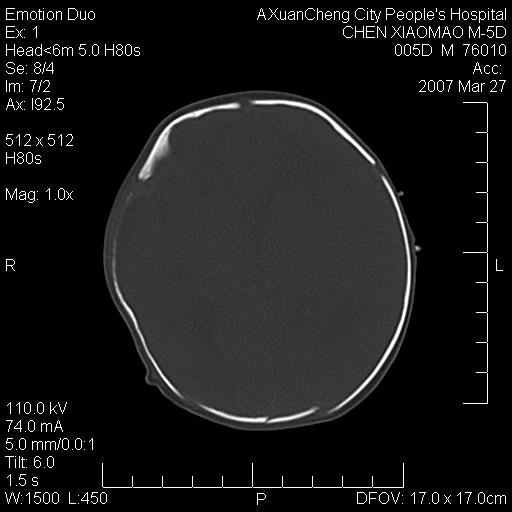

大家看看可有出血?另外枕骨中央是骨缝还是骨折

颅内未见明显异常。枕骨鳞部应为假缝(颅外软组织无肿胀),有外伤吗?

枕骨骨折可以下,应该比较明显,颅内还是正常的,不放心的话,短期随访。

未见明显异常,,那是横窦影,“缝”是后囟